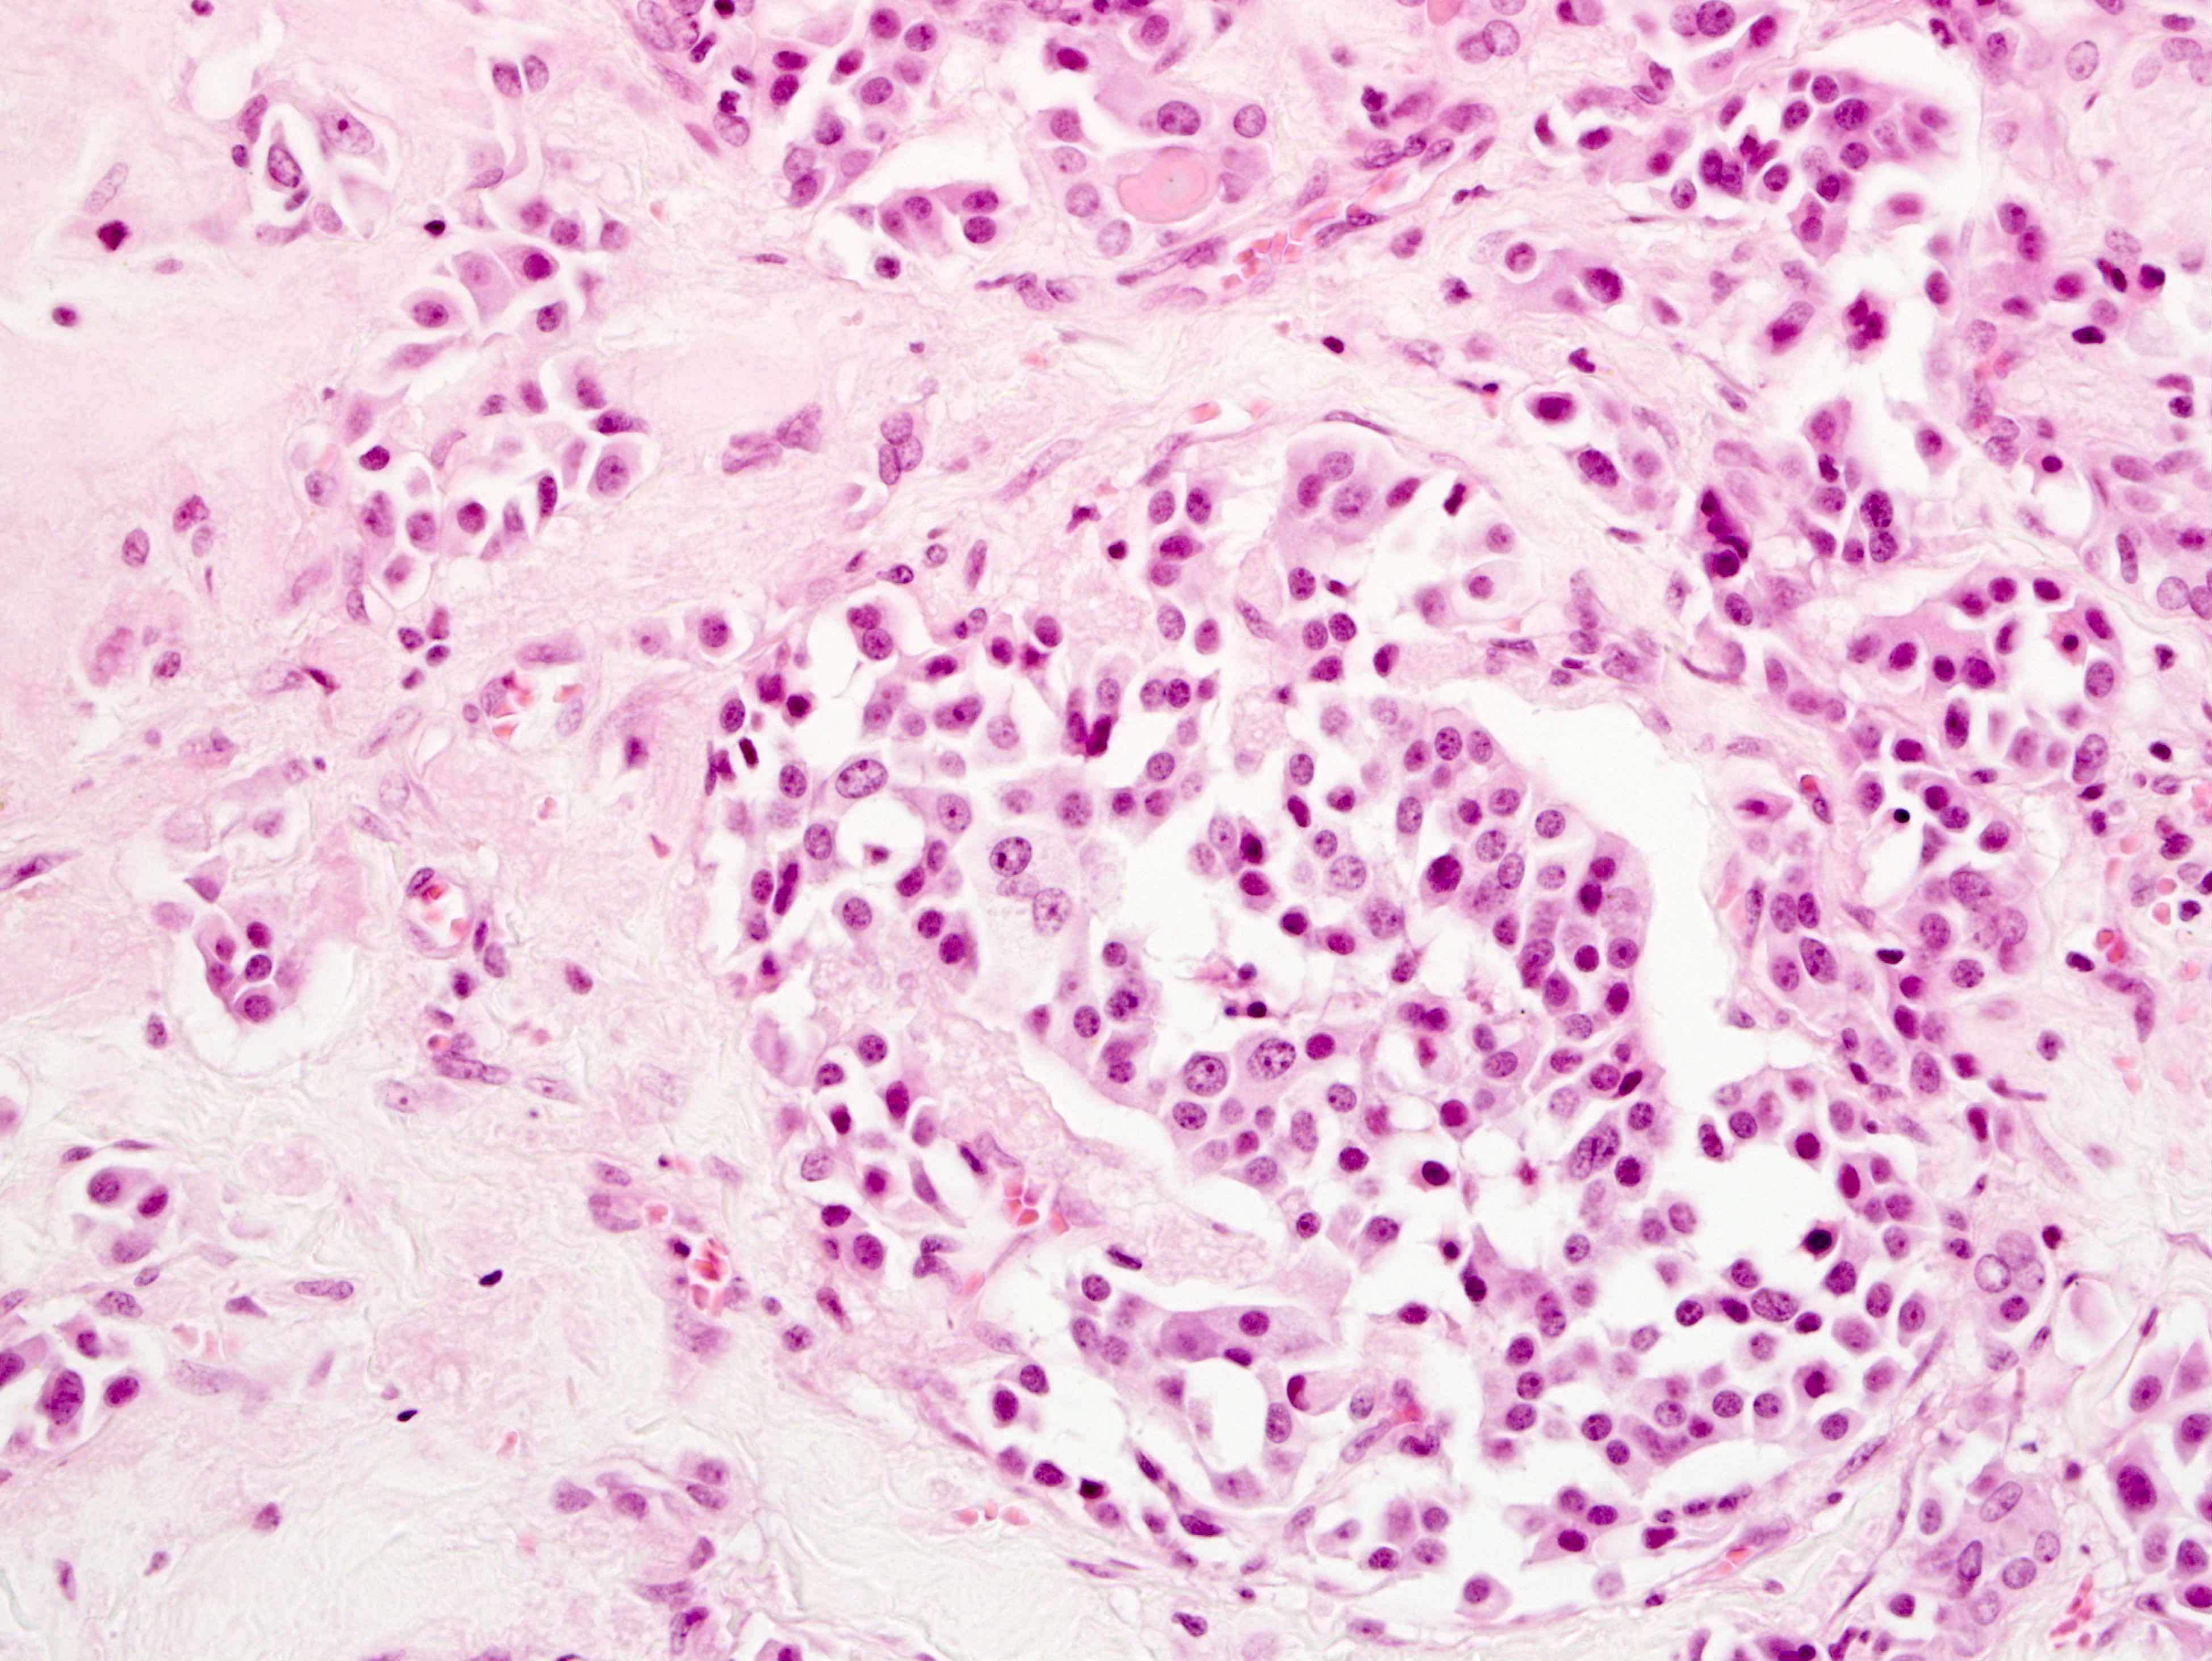

Microscopic (histologic) description

- Wide variety of morphology, can mimic any other thyroid malignancy

- Round, plasmacytoid, polygonal or spindle cells in nests, cords or follicles; often mixtures of these cells

- Round nuclei with finely stippled to coarsely clumped chromatin and indistinct nucleoli, occasional nuclear pseudoinclusion

- Eosinophilic to amphophilic granular cytoplasm due to secretory granules

- Generally low mitotic figures

- Stroma has amyloid deposits from calcitonin, prominent vascularity with glomeruloid configuration or long cords of vessels (Am J Surg Pathol 1995;19:642), coarse calcifications, occasional psammoma-like bodies

- Mucin in 42% (Arch Pathol Lab Med 1983;107:70)

- Often angiolymphatic invasion

- Occasionally marked neutrophilic infiltrate, oncocytic tumor cells, papillary patterns

Microscopic (histologic) images

Contributed by Shuanzeng Wei, M.D., Ph.D., Joseph Christopher Castillo, M.D. and Mark R. Wick, M.D.

AFIP images

Images hosted on other servers: